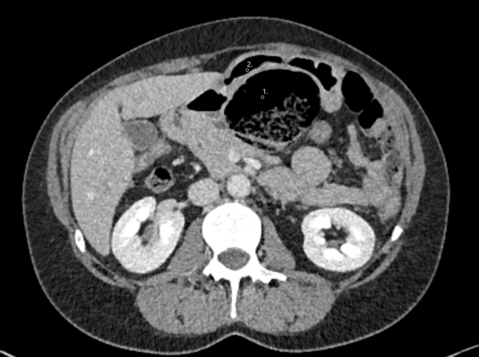

Given the patient's unexplained symptoms, an abdominal CT scan was performed:

The CT scan together with the clinical symptoms confirmed the suspicion of a symptomatic aortic aneurysm necessitating immediate intervention. There was suspicion on the CT scan for an aorto-duodenal fistula. The surgical procedure performed, was an open replacement of the aorta due to the juxtarenal location of the aneurysm and the suspected presence of an aorto-duodenal fistula. A vascular surgeon, assisted by a visceral surgeon, performed the surgery. During the surgery, no evidence of an aorto-duodenal fistula was identified, leading to the decision to replace the juxtarenal aorta with a Dacron interposition Graft. Due to positive blood culture results in the perioperative period, the patient received a long-term course of antibiotic treatment. The patient, who made nonetheless a satisfactory recovery and was discharged two weeks following the surgery, rejected our suggestion of a re-laparotomy for more radical aneurysmal sac debridement and omentoplasty given the high suspicion of a mycotic aneurysm. A PET-CT scan performed six months after the surgery, revealed a graft infection. Despite this finding, the patient expressed unwillingness to undergo further surgical intervention. At the time of publication, the patient is still alive under suppressive antibiotic regimen.

In this case, making the correct diagnosis was a challenge given the stable aneurysm dimensions in comparison to the previous imaging and due to the atypical clinical presentation. The suspicion of an aorto-duodenal fistula on CT scan prompted an open surgical approach. Due to the unfavorable anatomy for an EVAR, due to the very short infrarenal aortic neck, the possible strategy of a bridging procedure was not an option.